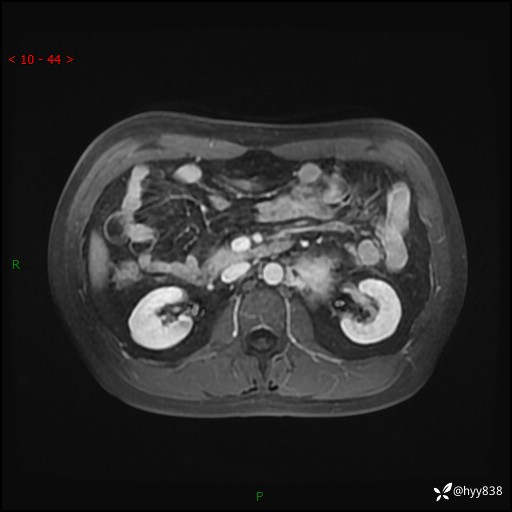

MRI增强